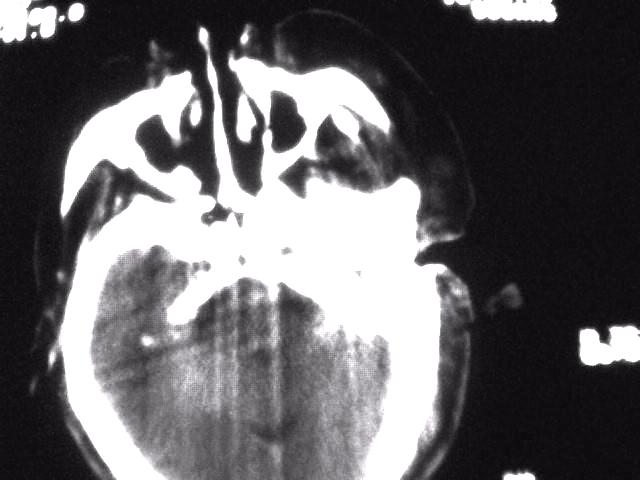

颈部层厚10mm间距10mm连续扫描及增强扫描共24层示:左侧下颈部胸锁乳突肌内侧区域内可见多发软组织结节,密度不均,内可见斑片状低密度区,大小不等,部分融合成块,左侧融合成一块者大约9.0x5.4,与周围肌肉、血管等结构界面不清,骨质未见明显浸润影。左侧锁骨下可见多个软组织结节,与周围界限尚清,左侧锁骨上窝内可见一大软组织肿物,大小约4.7x3.7cm,内密度欠均匀中心可见低密度区。

考虑:左侧颈部及双侧锁骨下多发淋巴结肿。非何杰金氏淋巴瘤可能性大,建议进一步检查。